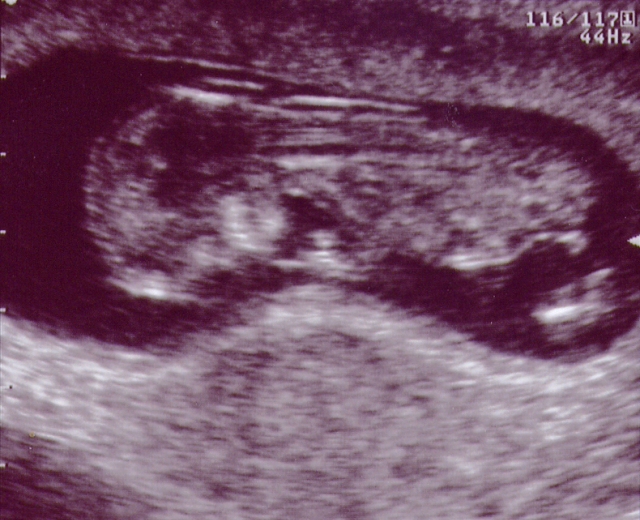

This is me at 12 weeks. Now you can see some of my body parts. It looks like I'm upside down because I am facing Mommy's back. I was too camera shy to turn around. I am just over 6 cm long -I still have a lot of growing to do to catch up to my big sister.